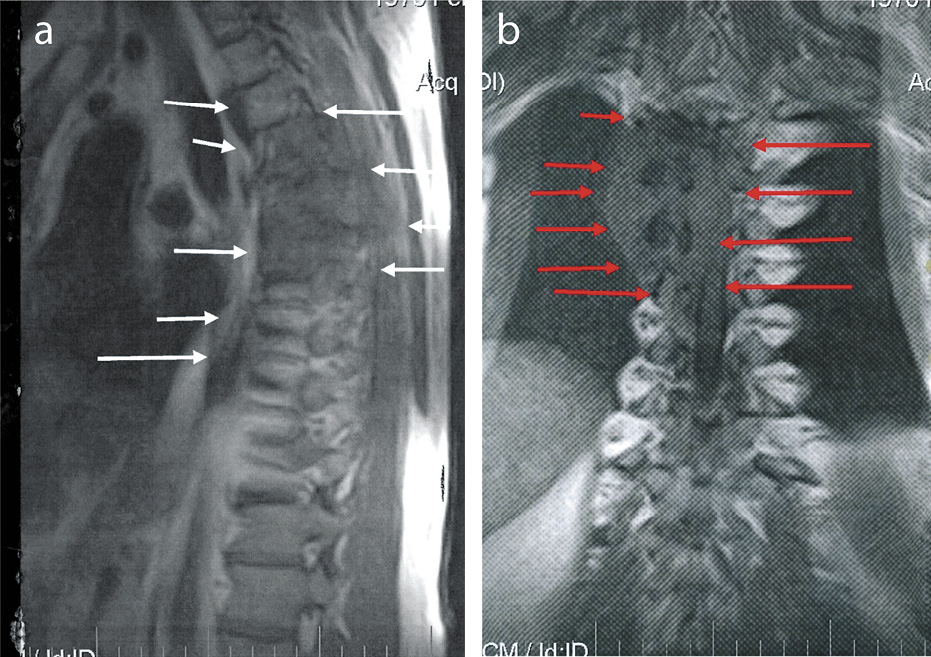

Пациент К., 71 год. В 2011 г. диагностирован светлоклеточный рак единственной левой почки. Проведено хирургическое лечение – резекция левой почки. В 2012 г. – местный рецидив опухоли, метастатическое поражение нисходящей ободочной кишки. Проведены ререзекция левой почки, а также удаление имплантационного метастаза нисходящей ободочной кишки. Прогрессирование онкопроцесса отмечено в марте 2014 г.: выявлены метастазы в забрюшинную клетчатку, имплантационные метастазы по брюшине. С июня 2014 г. – таргетная терапия сунитинибом с полным ответом после 2 курсов. Терапия сунитинибом продолжена, эффект сохранялся до марта 2016 г. В марте 2016 г. отмечено прогрессирование заболевания (метастазы в легких, в проекции резецированной почки, подкожной клетчатке). С марта 2016 по ноябрь 2016 г. – таргетная терапия эверолимусом. Эффект лечения – стабилизация, сохранявшаяся до ноября 2016 г. Ноябрь 2016 г. – прогрессирование заболевания (дальнейшее увеличение размеров узловых образований в подкожной клетчатке, в проекции резецированной почки, метастатические очаги в легких). С января 2017 по июнь 2017 г. – терапия бевацизумабом с временной стабилизацией. В июне 2017 г. отмечено дальнейшее прогрессирование опухолевого процесса (метастазы в печени, правом надпочечнике, легких). В июле 2017 г. начата терапия ниволумабом. При оценке эффекта через 2 мес иммунотерапии отмечено увеличение таргетных очагов в печени, проекции зоны резекции, в проекции правого надпочечника (рис. 1).

Рис. 1: а, b – увеличение таргетных очагов в печени (a – до начала иммунотерапии; b – через 2 мес иммунотерапии); c, d – увеличение таргетных очагов в проекции правого надпочечника и проекции зоны резекции (c – до начала иммунотерапии; d – через 2 мес иммунотерапии).

Но состояние пациента оставалось стабильным, дополнительных жалоб не предъявлял. Эффект лечения трактован как «неподтвержденное прогрессирование», лечение ниволумабом продолжено. На 4-м месяце иммунотерапии состояние пациента незначительно ухудшилось. Ухудшение состояния выражалось в появлении болей в подглазничной области слева, заложенности носа. При обследовании выявлено объемное образование в проекции левой верхнечелюстной пазухи. Выполнены биопсия образования, ангиография артерий головного мозга, эмболизация левой верхнечелюстной артерии. По данным гистологического и иммуногистохимического исследования операционного материала – метастаз почечно-клеточной карциномы в пазуху носа. В этот же период времени проведен контроль уже оцениваемых таргетных очагов, выявивший дальнейшее увеличение размеров очаговых образований в печени, проекции правого надпочечника, в проекции зоны резекции (рис. 2).